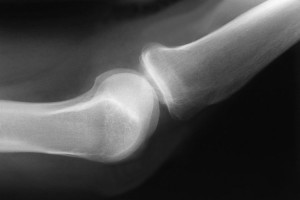

Las células madres para artritis y lesiones